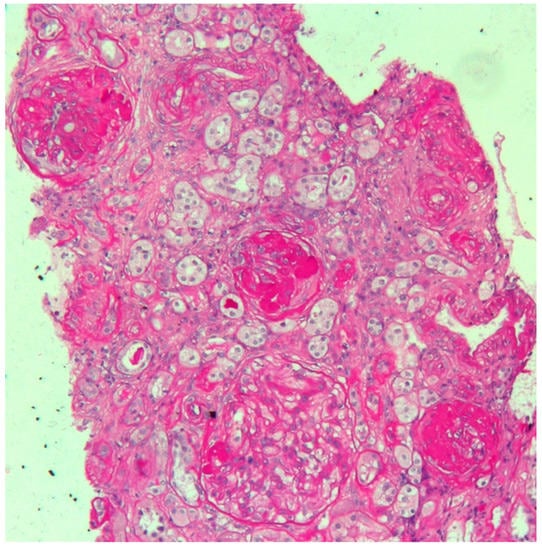

Electrocardiography suggested cardiac hypertrophy, confirmed at cardiac ultrasound, organised in the context of evaluations for kidney transplantation, which disclosed signs of relevant cardiac hypertrophy, out of proportion with her mild hypertension, confirmed at cardiac magnetic resonance (Figure 2, Figure 3 and Figure 4).

Figure 3. Echocardiographic findings. Echocardiographic findings show a moderate increase in LV thickness (max diameter 17 mm inferior and inferoseptal walls) in a four-chamber view (panel A) and on the mid short axis (panel B). Slightly reduced longitudinal function (S wave 0.07 cm/s) (D) and no significant abnormality of diastolic function (normal E/A pattern and E/E′ 10) were found (panel C and D) (Video S1 and Video S2).